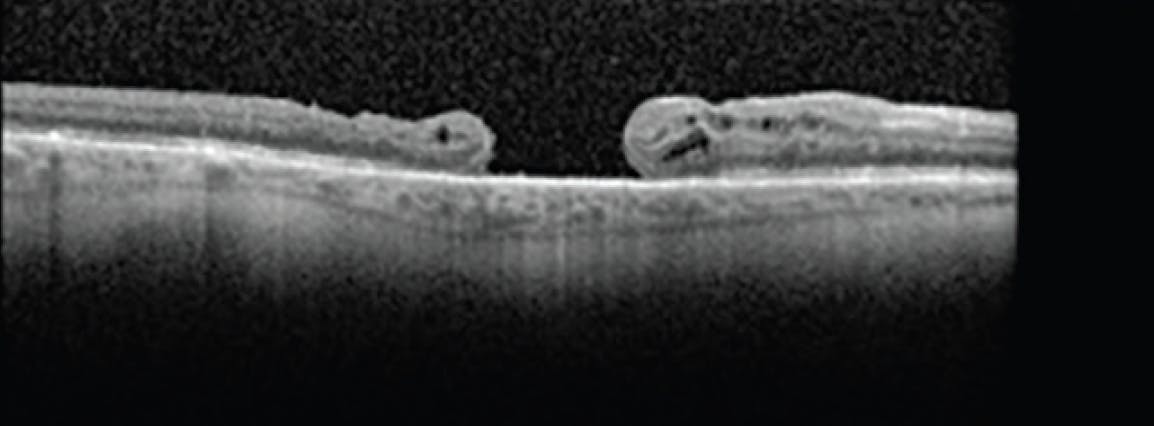

A 60-year-old man with a medical history of diabetes, hyperlipidemia, hypertension, and neovascular glaucoma in the left eye presented for a second opinion. He had developed an FTMH in his only seeing eye—the right eye—3 months prior and had undergone three unsuccessful PPV procedures with ILM peel and gas tamponade. His VA was counting fingers OD. OCT demonstrated an FTMH measuring approximately 1,000 µm with underlying retinal pigment epithelium (RPE) atrophy and no visible posterior hyaloid face (Figure 1). Alternative surgical options were discussed with the patient.

<p>Figure 1. OCT imaging showed a refractory primary FTMH of approximately 1,000 µm in the right eye of a 60-year-old man with a VA of counting fingers.</p>

Figure 1. OCT imaging showed a refractory primary FTMH of approximately 1,000 µm in the right eye of a 60-year-old man with a VA of counting fingers.